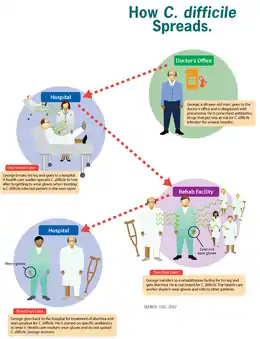

Clostridioides difficile infection is spread by bacterial spores found within feces.[1] Surfaces may become contaminated with the spores with further spread occurring via the hands of healthcare workers.[1] Risk factors for infection include antibiotic or proton pump inhibitor use, hospitalization, hypoalbuminemia,[8] other health problems, and older age.[1] Diagnosis is by stool culture or testing for the bacteria's DNA or toxins.[1] If a person tests positive but has no symptoms, the condition is known as C. difficile colonization rather than an infection.[1]

C. difficile is transmitted from person to person by the fecal-oral route. The organism forms heat-resistant spores that are not killed by alcohol-based hand cleansers or routine surface cleaning. Thus, these spores survive in clinical environments for long periods. Because of this, the bacteria may be cultured from almost any surface. Once spores are ingested, their acid-resistance allows them to pass through the stomach unscathed. Upon exposure to bile acids, they germinate and multiply into vegetative cells in the colon. People without a history of gastrointestinal disturbances due to antibiotic use or diarrheal illness are less likely to become colonized by C. difficile.[15]

People are most often infected in hospitals, nursing homes,[29] or other medical institutions, although infection outside medical settings is increasing. Individuals can develop the infection if they touch objects or surfaces that are contaminated with feces and then touch their mouth or mucous membranes. Healthcare workers could possibly spread the bacteria or contaminate surfaces through hand contact.[30] The rate of C. difficile acquisition is estimated to be 13% in those with hospital stays of up to two weeks, and 50% with stays longer than four weeks.[31]